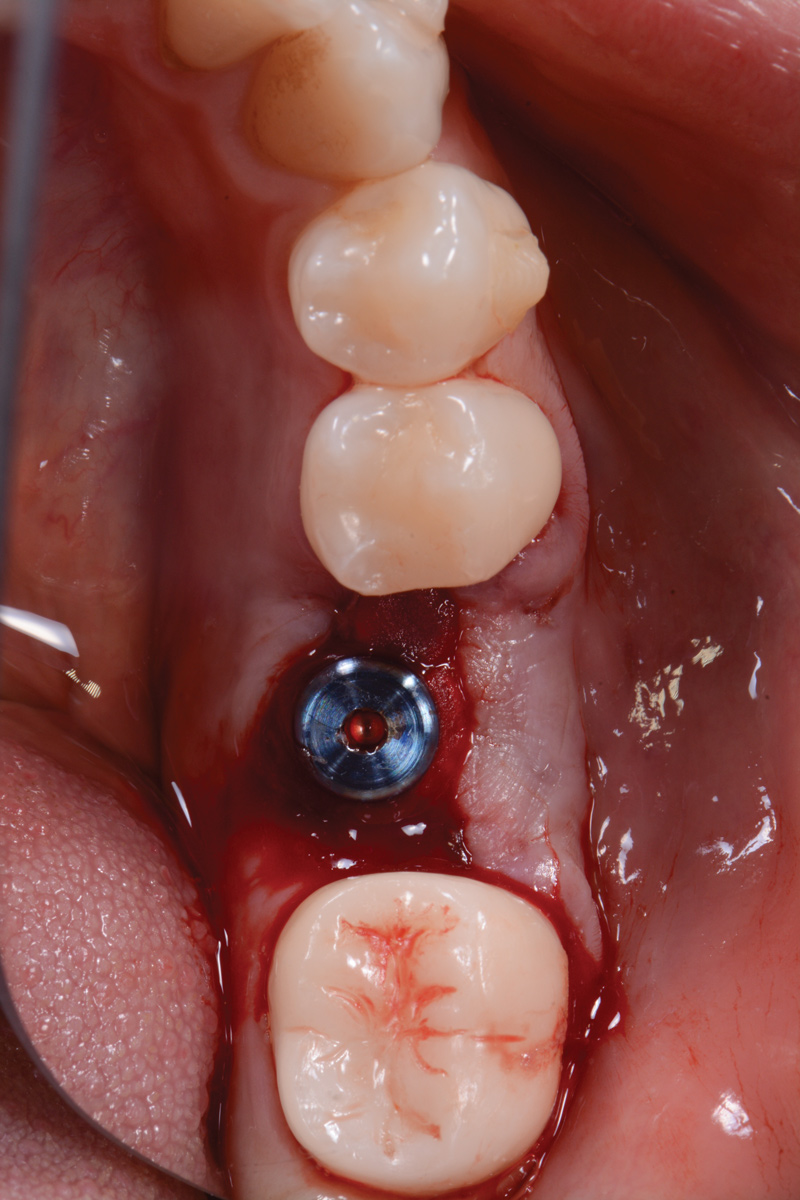

The following day, the patient presented for an emergency, reporting she began to bleed after she left the office and had continuous bleeding that day and night. Vital signs were normal (blood pressure was 115/65 mmHg, and pulse was 53 beats per minute). The first attempt to control the bleeding included having the patient bite on wet collagen wound dressing and alternate using wet- and dry-gauze compression for 30 minutes. After the removal of the collagen wound dressings, the bleeding restarted spontaneously. The sutures were then removed, and a collagen wound dressing was placed under the flap. Two single interrupted sutures were used, and a third suspended suture was placed around the healing abutment to obtain compression in the area. The patient was observed for 1 hour. During this time, wet-gauze compression was used on the area until the bleeding stopped. The patient was then dismissed and told to reapply gauze with pressure if bleeding recurred (Figure 1 through Figure 5).

Fig 3. Wound dressing in place.

Figure 3

Fig 4. Wound dressing secured with two single interrupted sutures and one suspended resorbable suture.

Figure 4